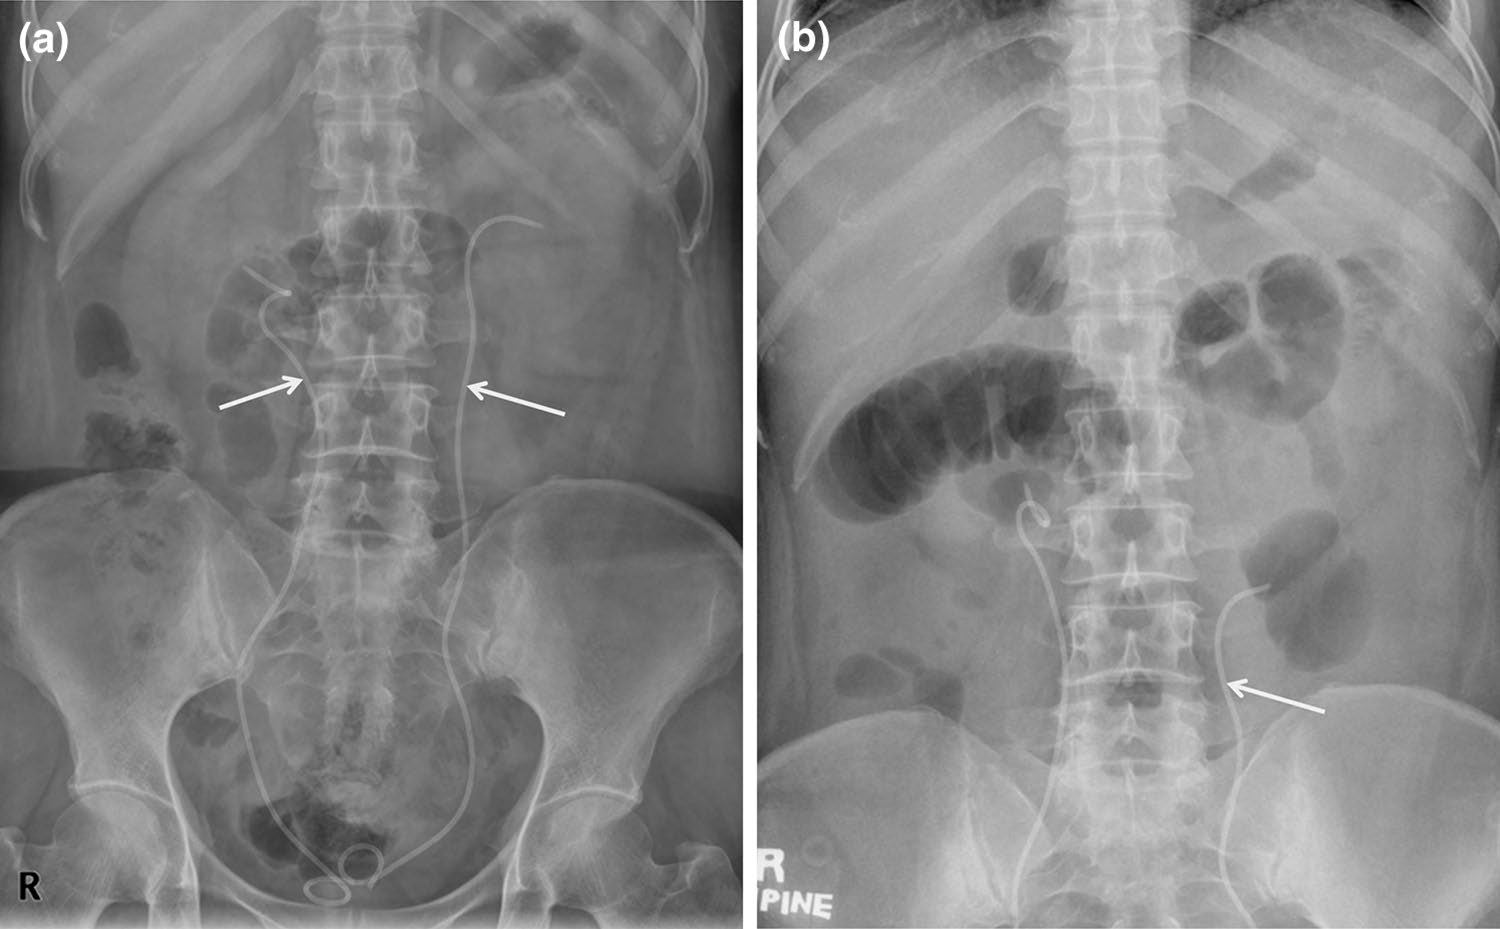

输尿管支架

输尿管支架通常用于治疗输尿管梗阻或瘘(图4)[7]。支架的近端和远端部分设计为J形或猪尾形,以防止从输尿管迁移。然而,由于蠕动作用,支架仍可能发生迁移(图5)[7]。